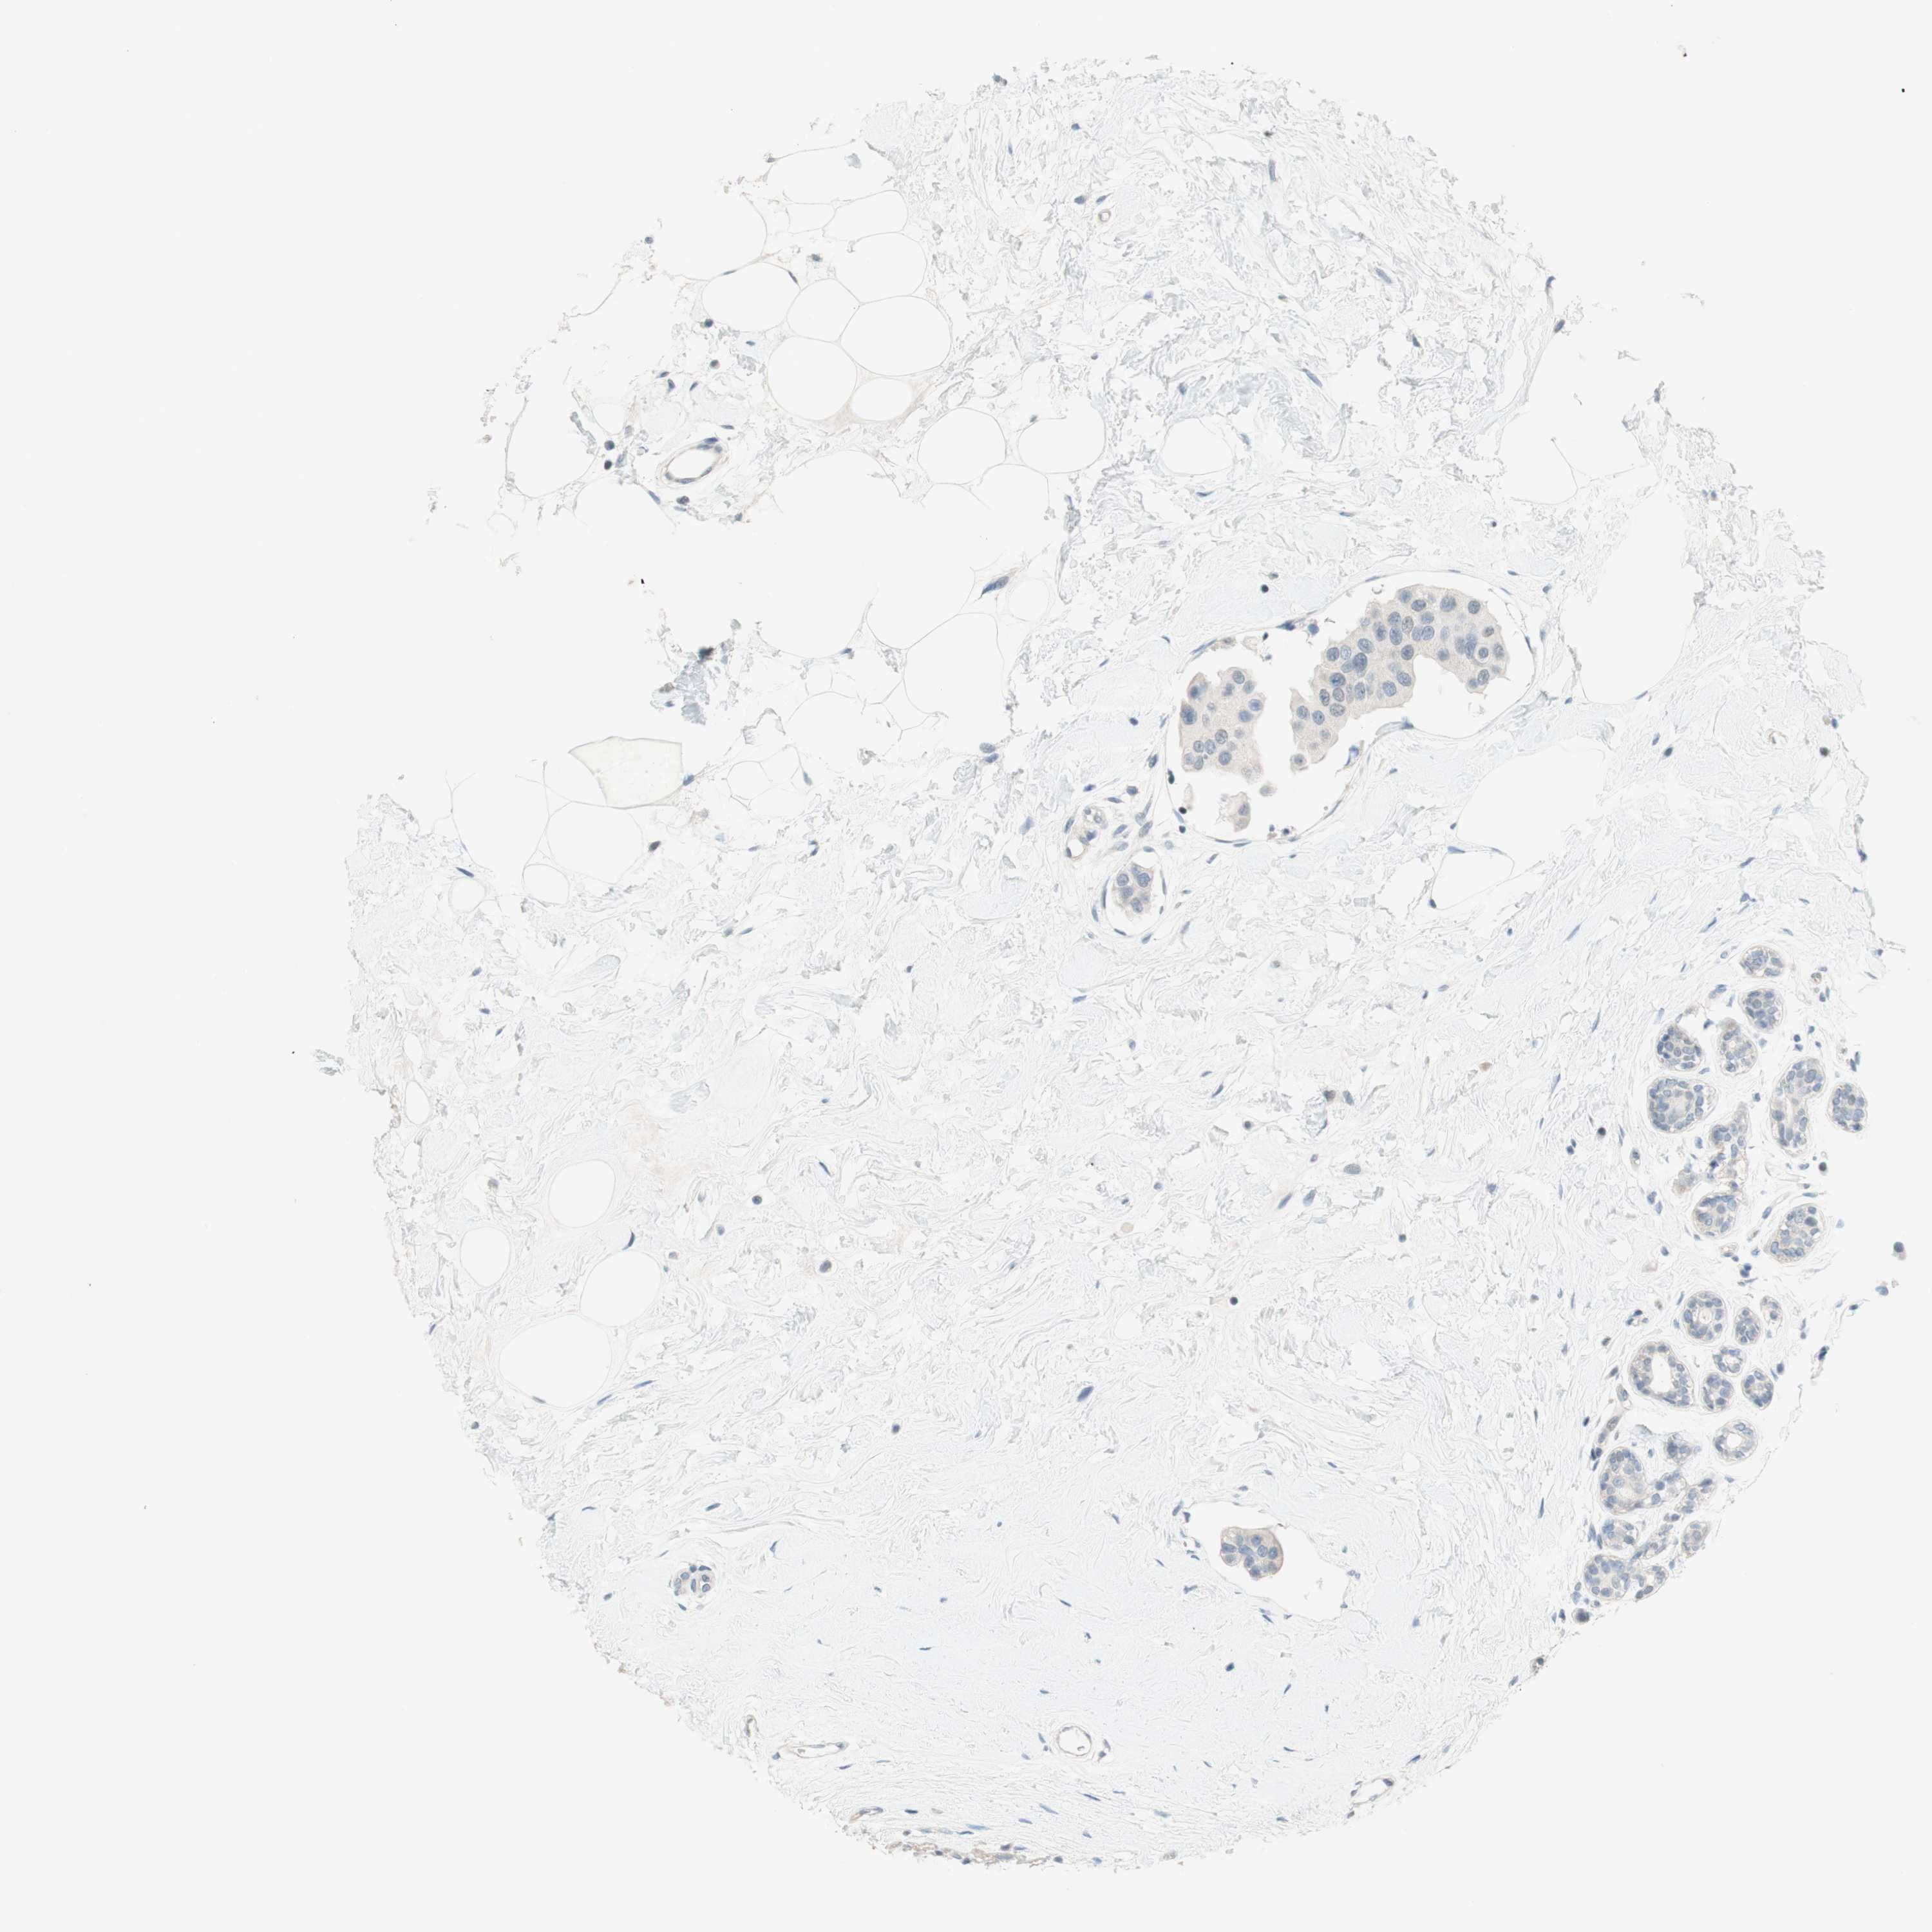

CANCER BREAST CANCER Show tissue menu

BRCA TCGA BRCA VALIDATION PROTEIN EXPRESSION